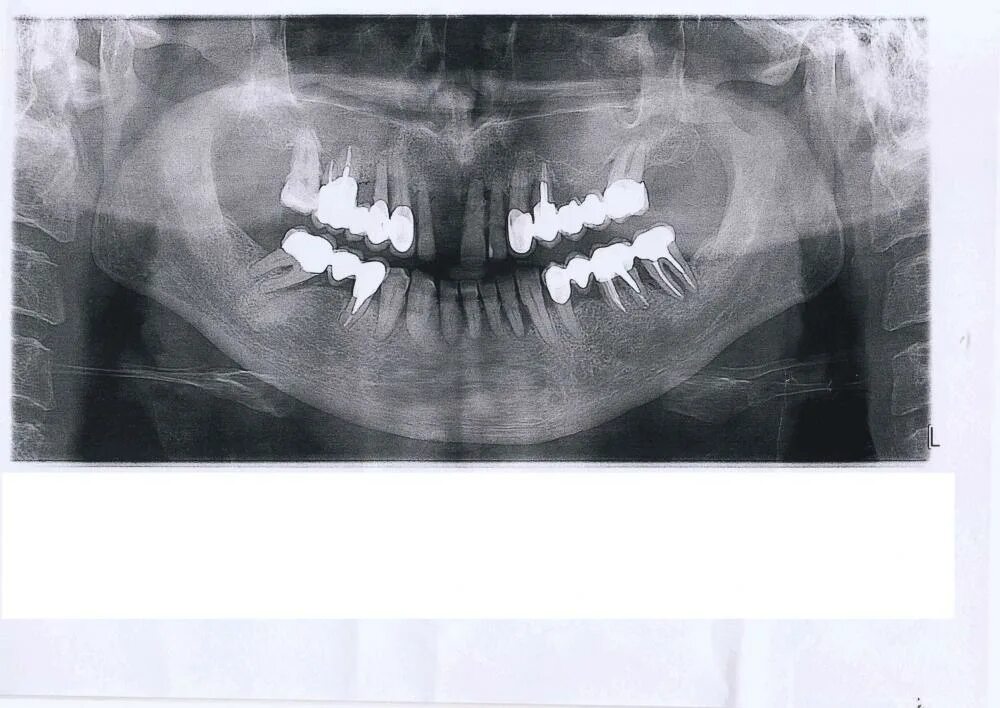

Поставить 4 зуба